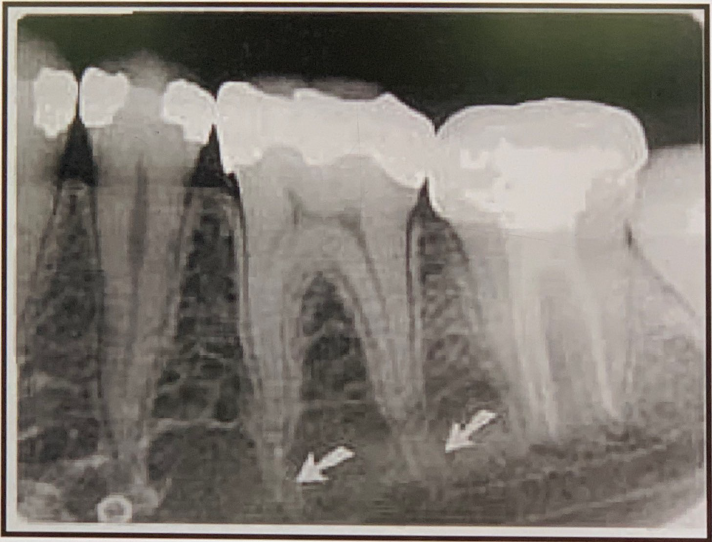

97. What is showing by arrow?

Nutrient Canals: carry a neurovascular bundle and appear as radiolucent lines of uniform width. most often seen on mandibular periapical radiographs running vertically from the inferior dental canal directly to the apex of a tooth or into the interdental space between the mandibular incisors. may appear as a small round radiolucency if they are oriented perpendicular to the cortex.